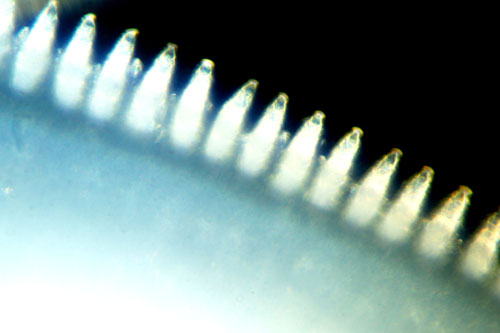

- Hirudin Hirudin (derived from Hirudo medicinalis = medicinal leech) is one of the active ingredients in leech saliva that is used independently as a medicinal product. Hirudin inhibits blood clotting by binding to and blocking thrombin. Calin and saratin, two further anticoagulants, block the effects of the von Willebrand factor. They are responsible for the prolonged bleeding after a leech therapy session, which causes a gentle bloodletting process and enables the wound to clean itself. Leech therapy sessions should last for a maximum of 60 minutes, during which time it is important for the leech to keep the wound open and the blood flowing.

- Destabilase dissolves fibrin and blood clots, while apyrase prevents platelet activation.

- As the leech sucks, hyaluronidase and collagenase loosen the tissue so that active ingredients in the saliva can penetrate deeper.

- Eglin C and LDTE (Leech-derived tryptase inhibitor) both have anti-inflammatory properties.

- Antistasin expands the blood vessels and thus ensures improved blood circulation.

- Der Destabilase is also said to have an antimicrobial effect